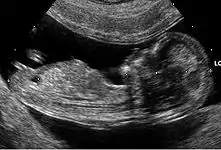

Embryon à 8 semaines

L'embryon mesure entre 15 et 22 mm. La vésicule vitelline qui le nourrit est juste à côté. À la fin de cette semaine, les coudes deviennent visibles